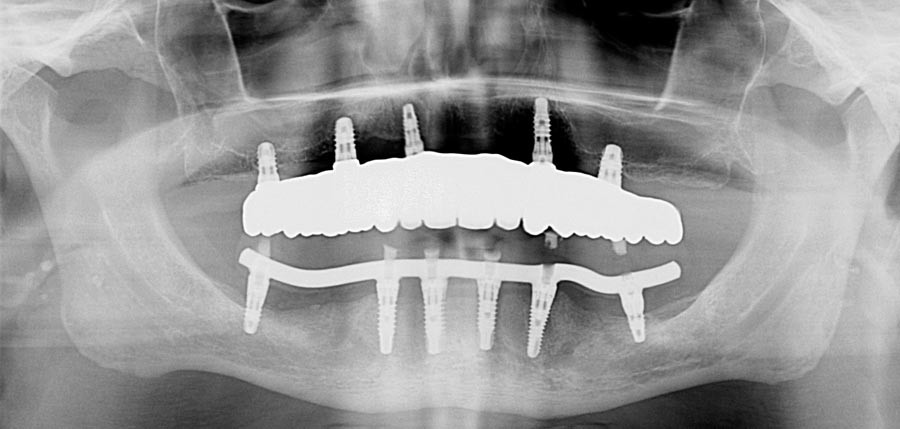

Occlusal (mirror) view of the upper implants. This patient had good bone in these five areas. If the bone was better we would have added a sixth implant.

Final upper zirconium implant bridge. Final lower titanium/acrylic bridge. For patients with grinding habits, I recommend different materials in the opposing jaws to decrease the chances of breakage. Here, the lower acrylic teeth are softer than the upper zirconium which allows for tooth wear (attrition) instead of breakage.